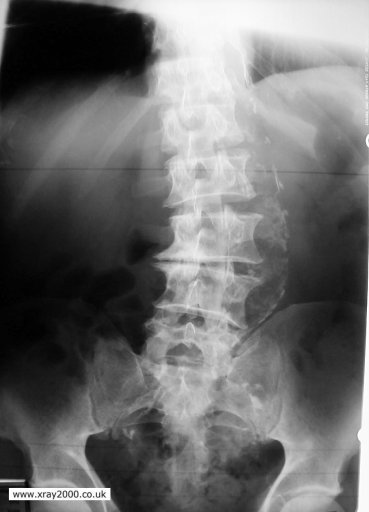

These scans are of the same spine- why are the BMD measurements so different

The spine is osteoarthritic- this transiently increases BMD, so has to be considered in the calculations

How does osteoarthritis appear on a DXA scan?

Bright white spots